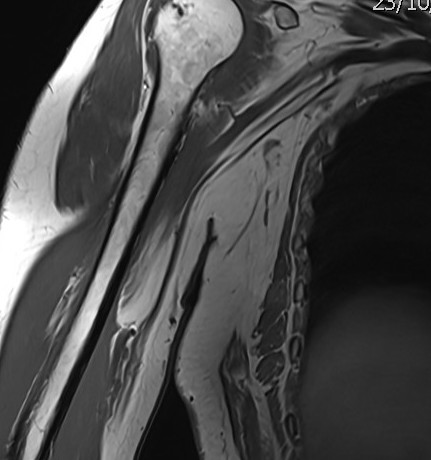

Ante estos hallazgos sin saber concretar la naturaleza clara de la lesión, se solicita una resonancia magnética (RMN) preferente. La RMN informa de una lesión homogénea, bien definida, dependiente del músculo coracobraquial, de 35 × 18 × 82 mm, con finos septos internos sin engrosamientos nodulares, compatible con lipoma intramuscular.

El principal diagnóstico diferencial es el liposarcoma, especialmente por el tamaño y localización profunda. La ausencia de engrosamientos nodulares y la homogeneidad en la imagen apoyan la benignidad.